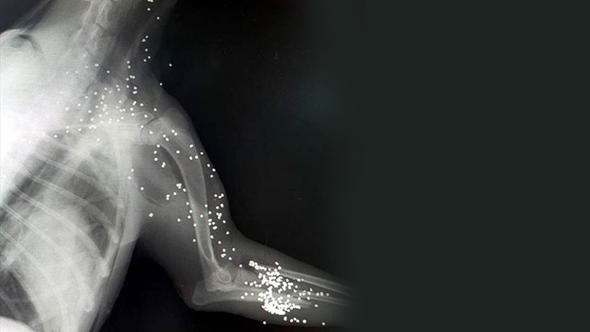

Bodrum’da Ortakent Mahallesi Kurudere Deresi etrafında yürüyüş yapan vatandaşlar, dere yatağı içerisinde kanlar içinde yatan bir köpek fark etti. Köpeğin yanına yaklaştıklarında yarı baygın halde olduğunu gören hayvanseverler, köpeği acil olarak veterinere götürdü. Röntgeni çekilen köpeğin vücudunda 300 saçma tespit edildi. Ön ayağının da kırık olduğu görülen köpek acil olarak ameliyata alındı. Yapılan ameliyatla 145 saçma köpeğin vücudundan çıkarılırken, kırık olan ayağı da sargıya alındı. Köpeğin hayati tehlikesinin devam ettiği öğrenildi.

Av tüfeği ile vurulduğu tespit edilen köpeğin röntgeni şoke etti. Bodrum Hayvan Hakları Derneği Başkanı Füsun Uslu, köpeği ayağını kırdıktan sonra kurşun yağmuruna tutan kişi veya kişilerden Bodrum İlçe Emniyet Müdürlüğüne giderek şikayetçi olacağını söyledi.